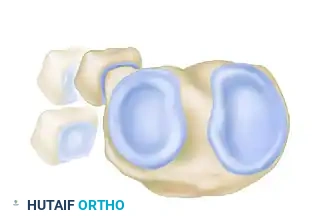

The PTFJ is a synovial joint between the lateral condyle of the tibia and the head of the fibula. Ogden classified the anatomical variants of this joint into two basic types based on the inclination of the articular surface:

FIGURE 60-7: Two basic types of proximal tibiofibular joints according to Ogden. The horizontal type is generally more stable, whereas the oblique type is more prone to rotational displacement and dislocation.